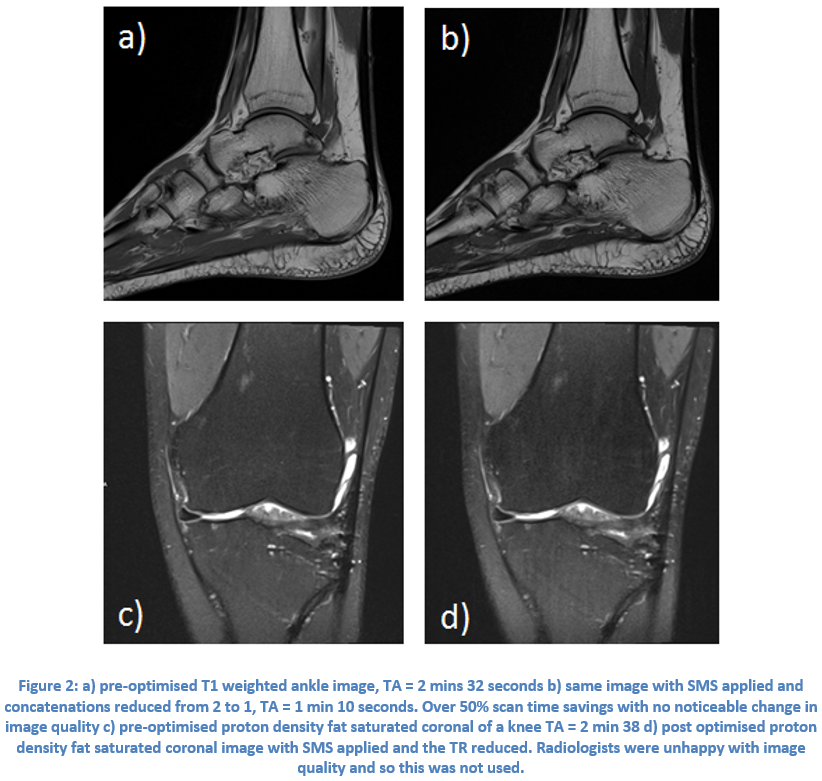

Case Study 1: Multi-Slice in Musculo-Skeletal MR on Siemens Sola (XA31)

Mr Matthew Marzetti, Leeds Teaching Hospitals NHS Trust